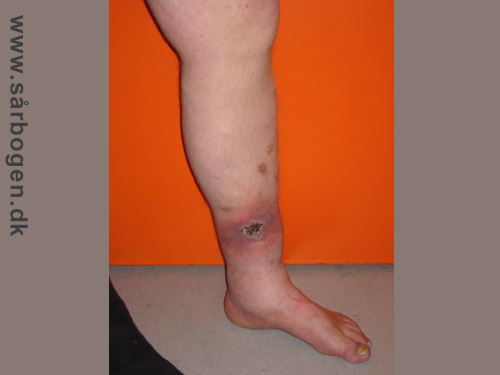

Charcot i ankel

Zoom